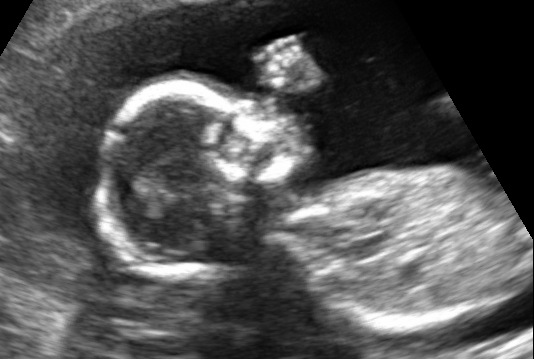

показывали нам нашего ребеночка во всей красе...он нам ручками махал....и что то пытался говорить)))...чесал носик, ножки выпрямлял и выгибался))) такой прикольный! сидел он на попе поэтому чтобы посмотреть его делали ещё и внутреннее узи))) и вот показывают нам ии говорят это ваш половой орган...я смотрю и вижу что это МАЛЬЧИК!!!!!!!!!!!! висит писяка такая смешная))) так что будет у нас братик!))) самое главное что он у нас здоровенький! самый красивый)))) папе я сказала что он похож на меня)))) подумали что Илюшке с братиком будет очень интересно расти)))) будут друг за друга всегда))) Папа позже пообещал ещё и сестренку нам)))) я очень счастлива! Точнее все мы безумно счастливы))) пошли в кафе и отметили это событие как следует/ целую вас мои девочки так что у нас теперь мальчонок)))